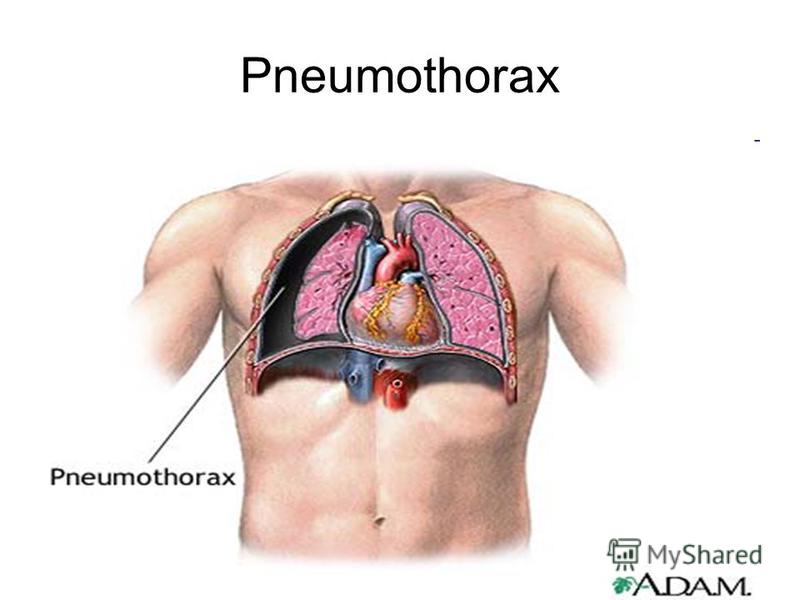

Схемы дыхания: Пневмоторакс на изображениях